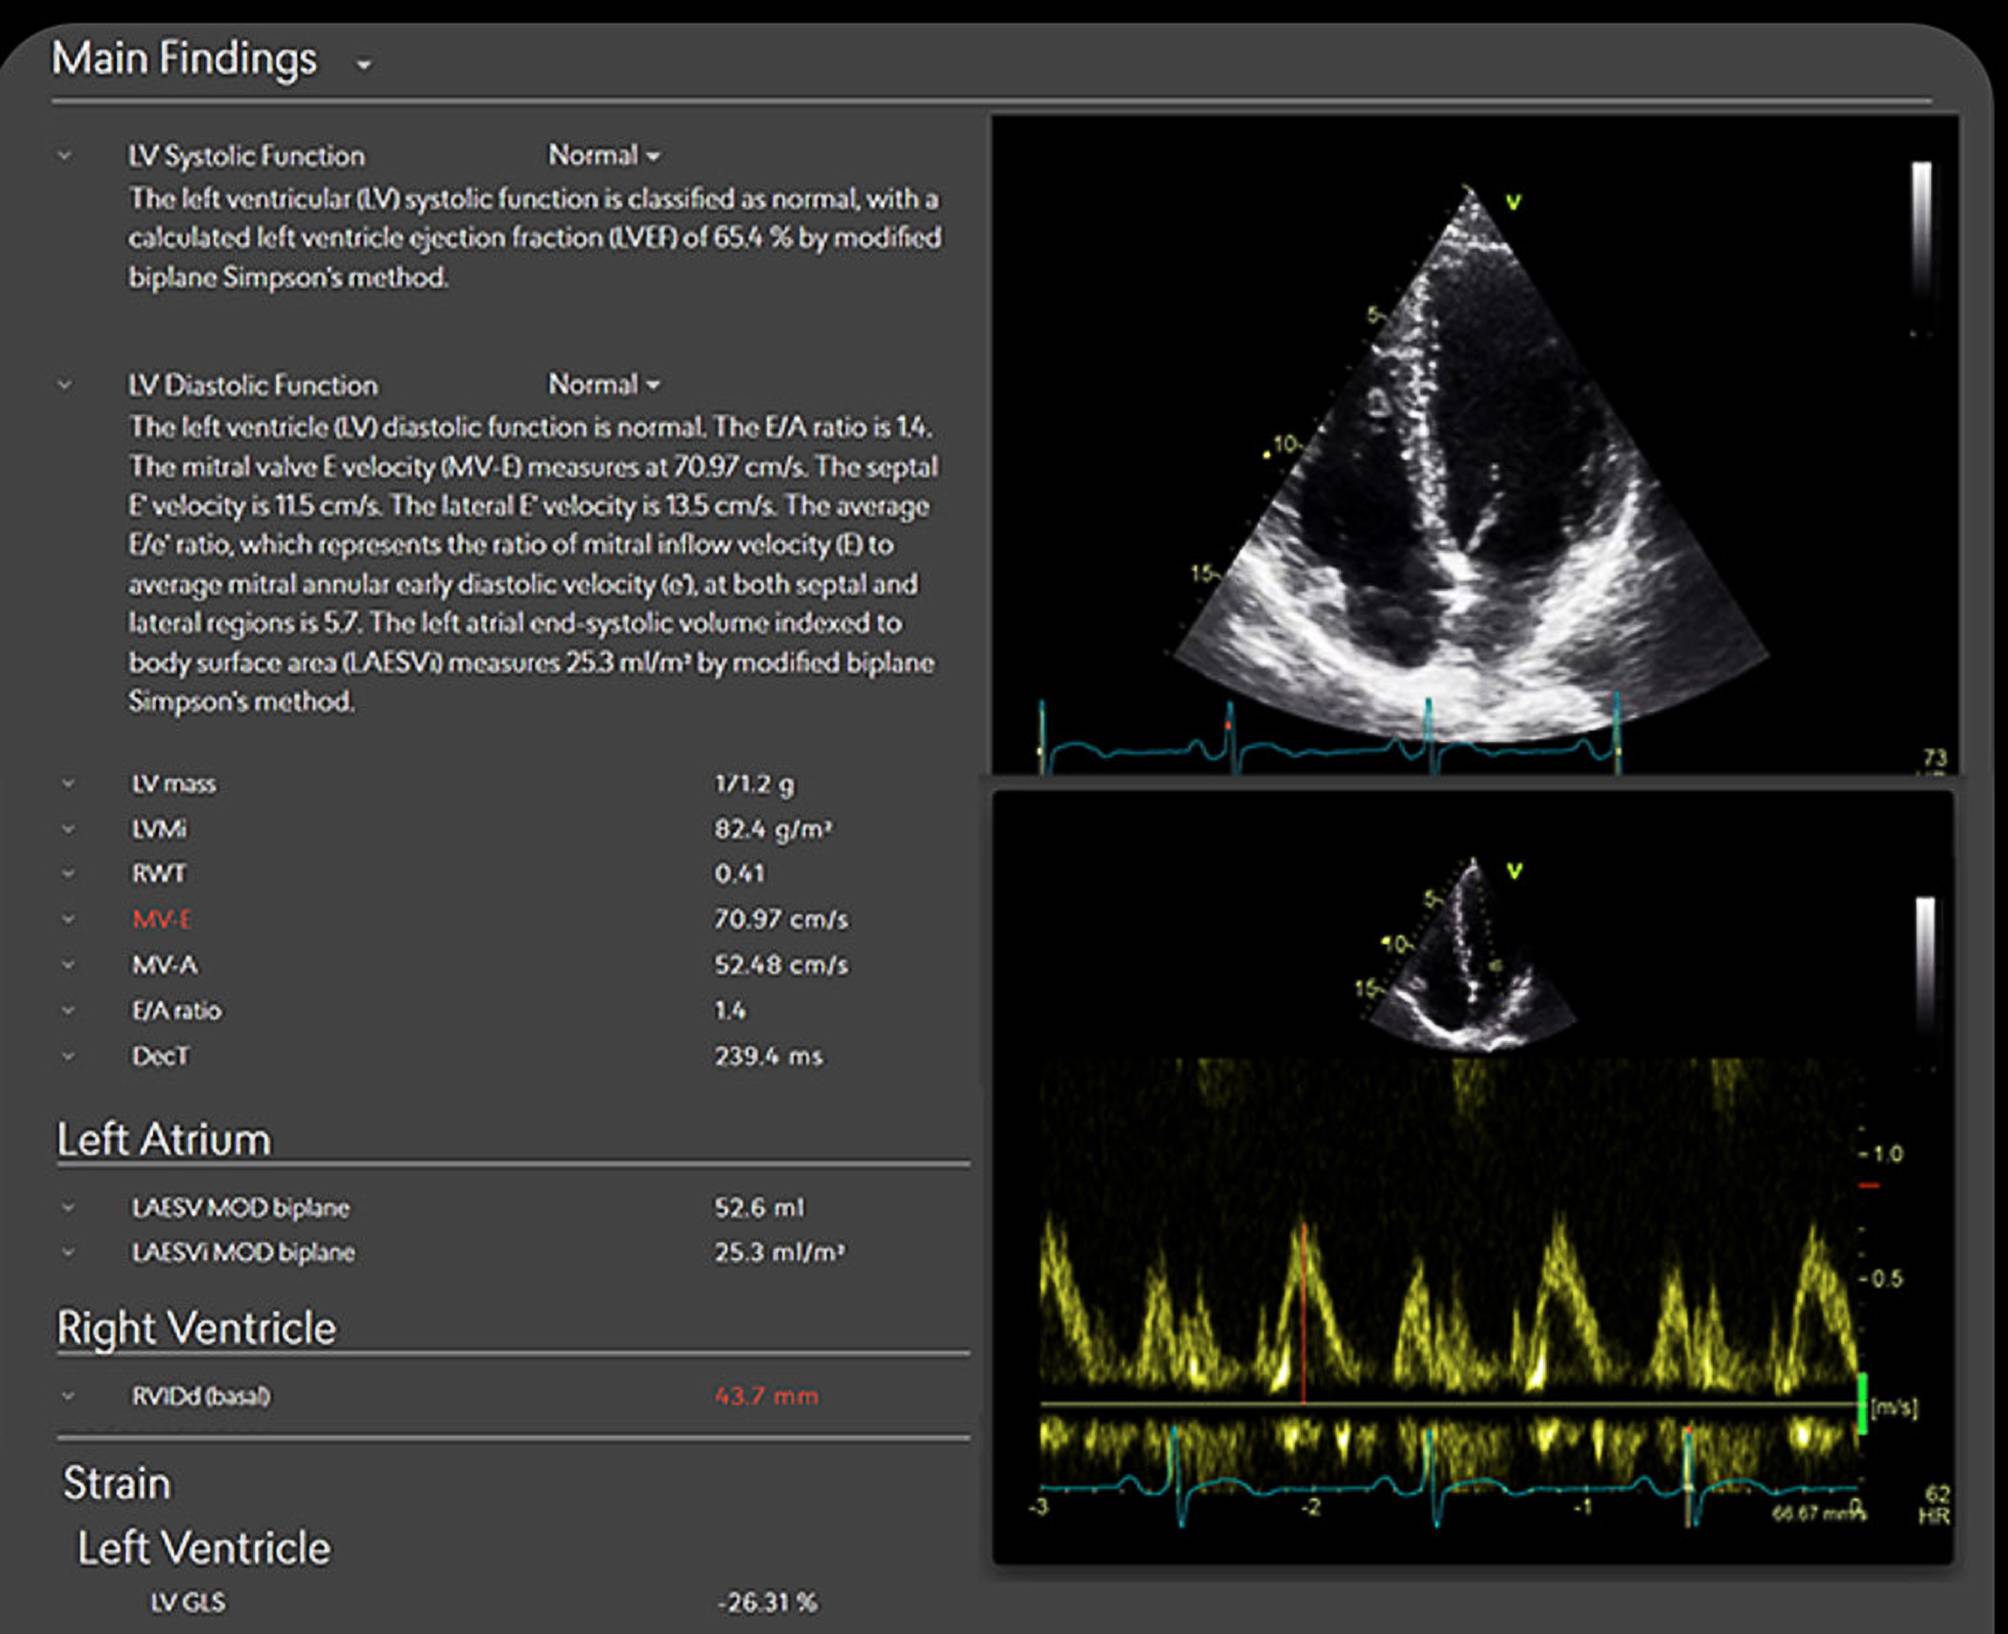

Fig. 1

AI-generated echocardiography report using Us2.AI. Example of an automated report displaying measurements for systolic and diastolic function, left atrial volume, right ventricular size, and strain, with editable contours and Doppler tracings. All outputs are presented in a guideline-aligned format, allowing clinician review and adjustment